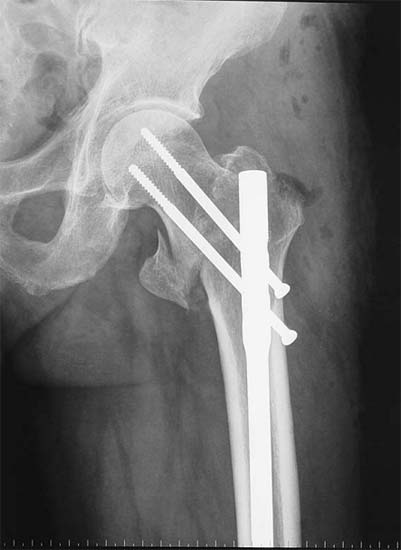

股骨粗隆间骨折,采用闭合股骨重建钉内固定。